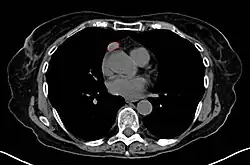

• CT scan

• MRI yield over CT minimal

• Thymoma typically presents in the anterior/superior mediastinum